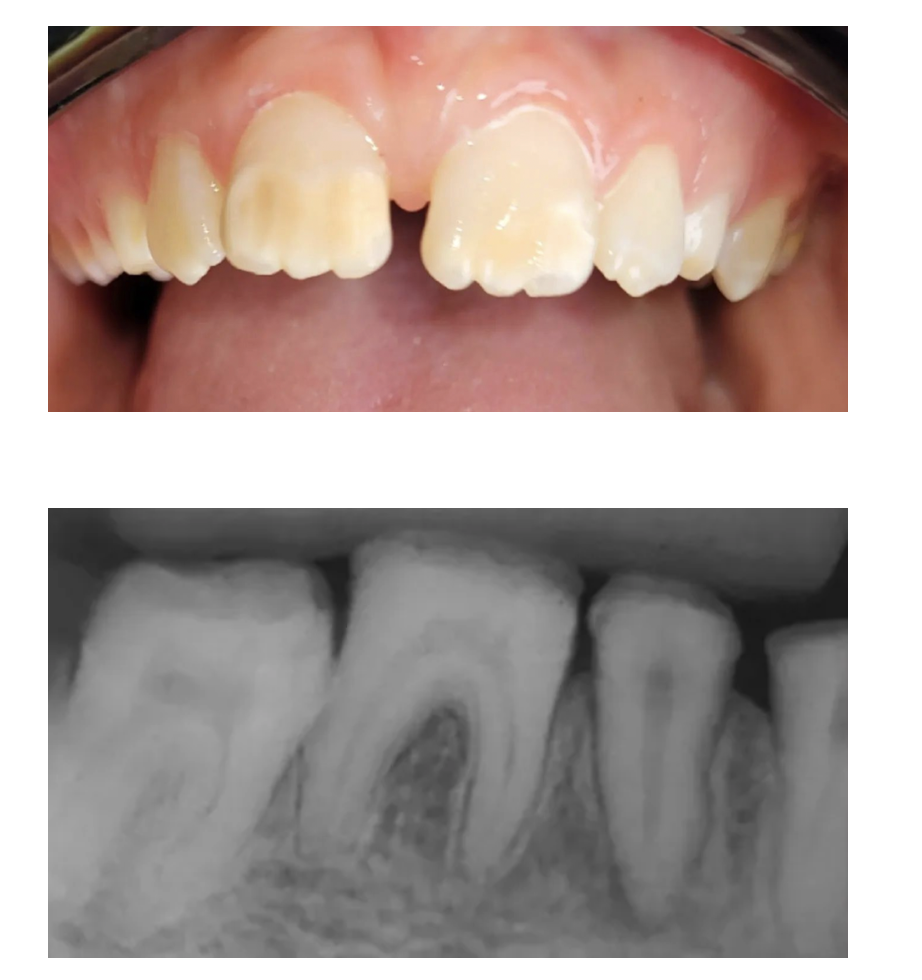

Amelogenesis Imperfecta

A

Intrinsic alteration of the ENAMEL

* Normal Dentin and Pulp

Teeth can be:

* discolored (yellow/brown)

* pitted

* thin

Type 1: Hypoplastic

*. Affects quantity of enamel

Type 2: Hypomaturation

* affects quality and quantity of enamel

Type 3: Hypocalcified

* affects quality of enamel

Tx: Full coverage crowns for cosmetics